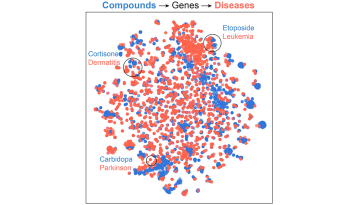

A continuació es mostren alguns projectes destacats que van rebre finançament el 2022 mitjançant convocatòries tant competitives com no competitives per part d’entitats públiques i privades. Aquests i altres projectes estratègics han pogut avançar gràcies a l’ús de tecnologies d'última generació, com ara l'aprenentatge automàtic, la intel·ligència artificial i la seqüenciació de cèl·lules úniques.